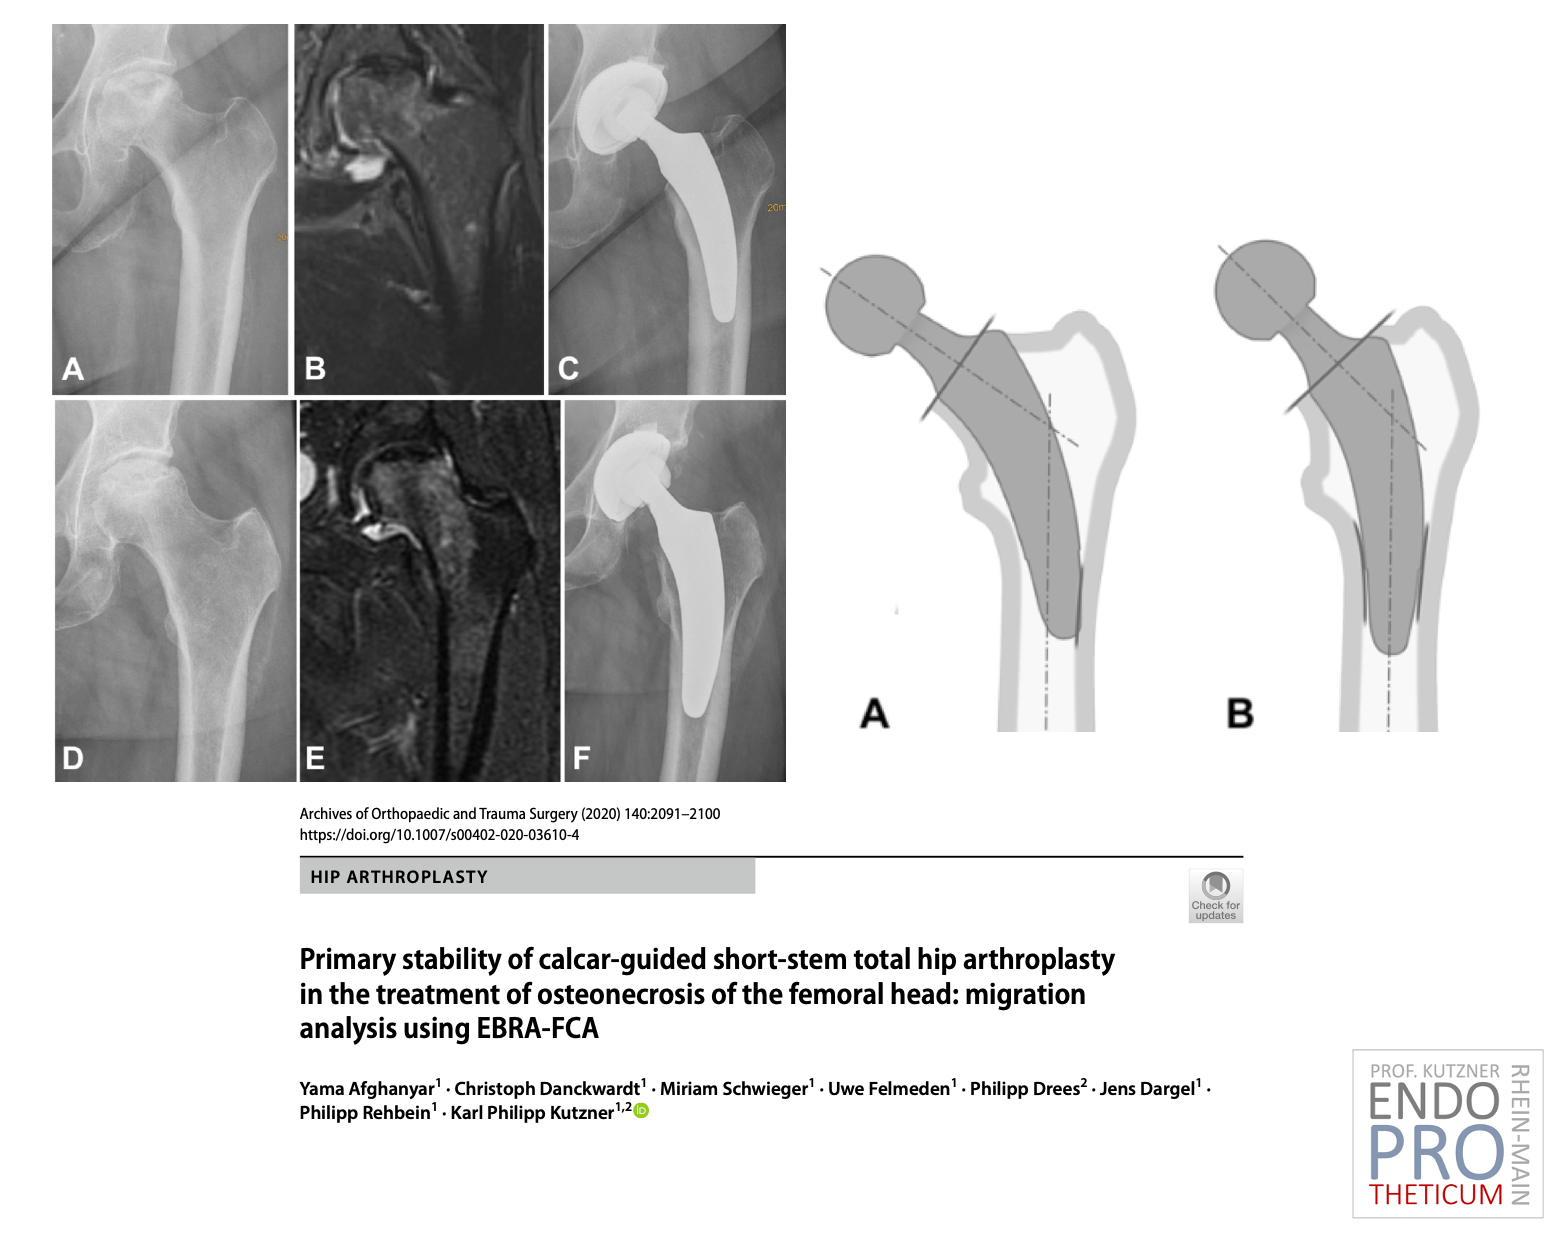

The concept of modern calcar-guided short stems in hip arthroplasty aims at the precise reconstruction of the individual, anatomical hip geometry. This involves a

bone- and soft tissue-sparing implantation technique in conjunction with a physiological load on the joint-proximal part of the femur, used to preserve the bone in the long term.